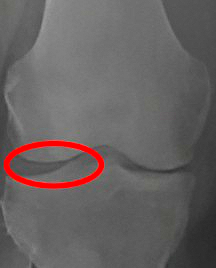

병원에 가보니 양쪽 무릎에

관절염이 진행된 지 꽤 시간이 지났고